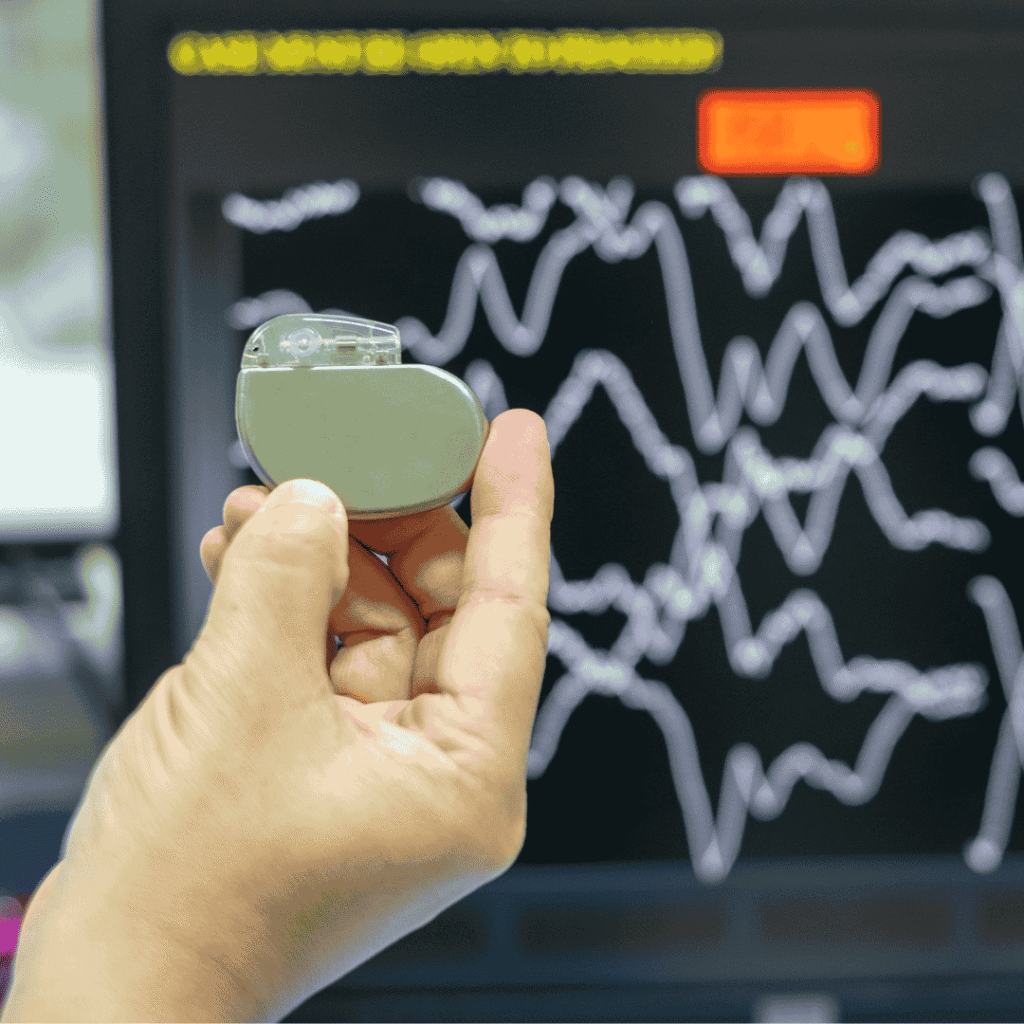

What Is Pacemaker Implantation?

Pacemaker implantation is a life-saving procedure designed to regulate the heartbeat in patients with arrhythmias or irregular heartbeats. This small device helps control heart rate, ensuring the heart beats at a proper rhythm.